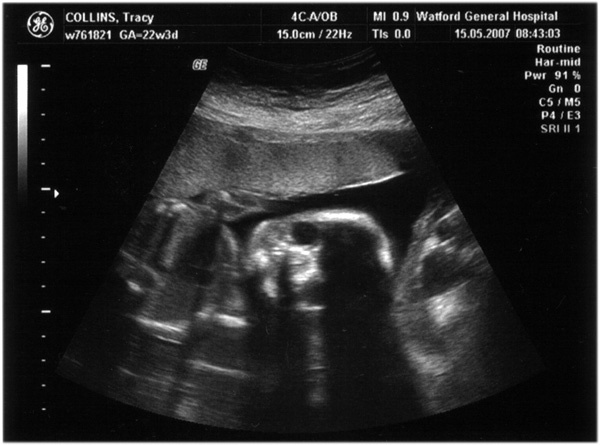

Third scan, 15th May 2007, (21 weeks)